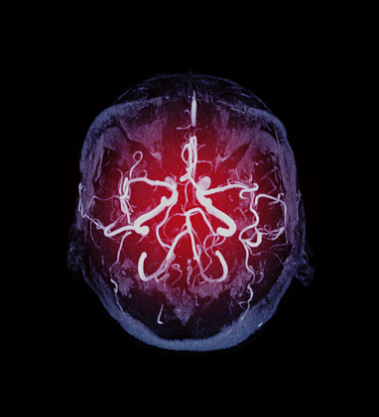

뇌경색은 뇌에 산소를 공급하는 뇌혈관이 막히거나 다른 곳에서 색전물질이 혈관을 통해서 전달되어 혈관을 막아 뇌세포가 파괴되고 그로 인하여 신체적, 정신적 장애가 생기는 질환을 말합니다.

뇌경색은 우리나라 단일 질환 사망원인 1위일 정도로 치명적인 질환으로 전 세계적으로는 매년 600만명이 뇌경색으로 사망한다고 합니다. 뇌경색은 사망률이 높을 뿐 아니라 사망하지 않더라도 그 후유증이 굉장히 심한 것으로 알려져 있는데요.